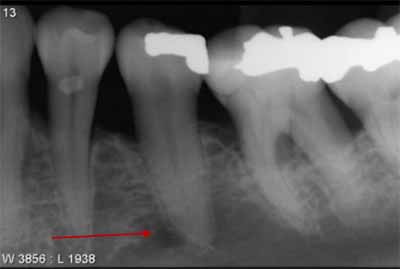

上顎のさらに奥には、臼歯があります。この領域には、X線画像に投影されるさまざまな解剖学的構造がいくつかあります。上顎洞の下部(画像10および画像14を参照)がさらに詳しくわかり、多くの場合、外後頭隆起も確認できます。この構造はエックス線不透過性が高く、「U」または「V」の文字のような形をしています。外後頭突起は主に上軸投影時に画像化され、大臼歯の歯根尖と重なる可能性があり、病変が隠れる危険性があります(画像13を参照)。

頬骨突起の遠位側には頬骨弓の下縁があり、わずかにエックス線不透過性の弓として描かれています (画像13を参照)。